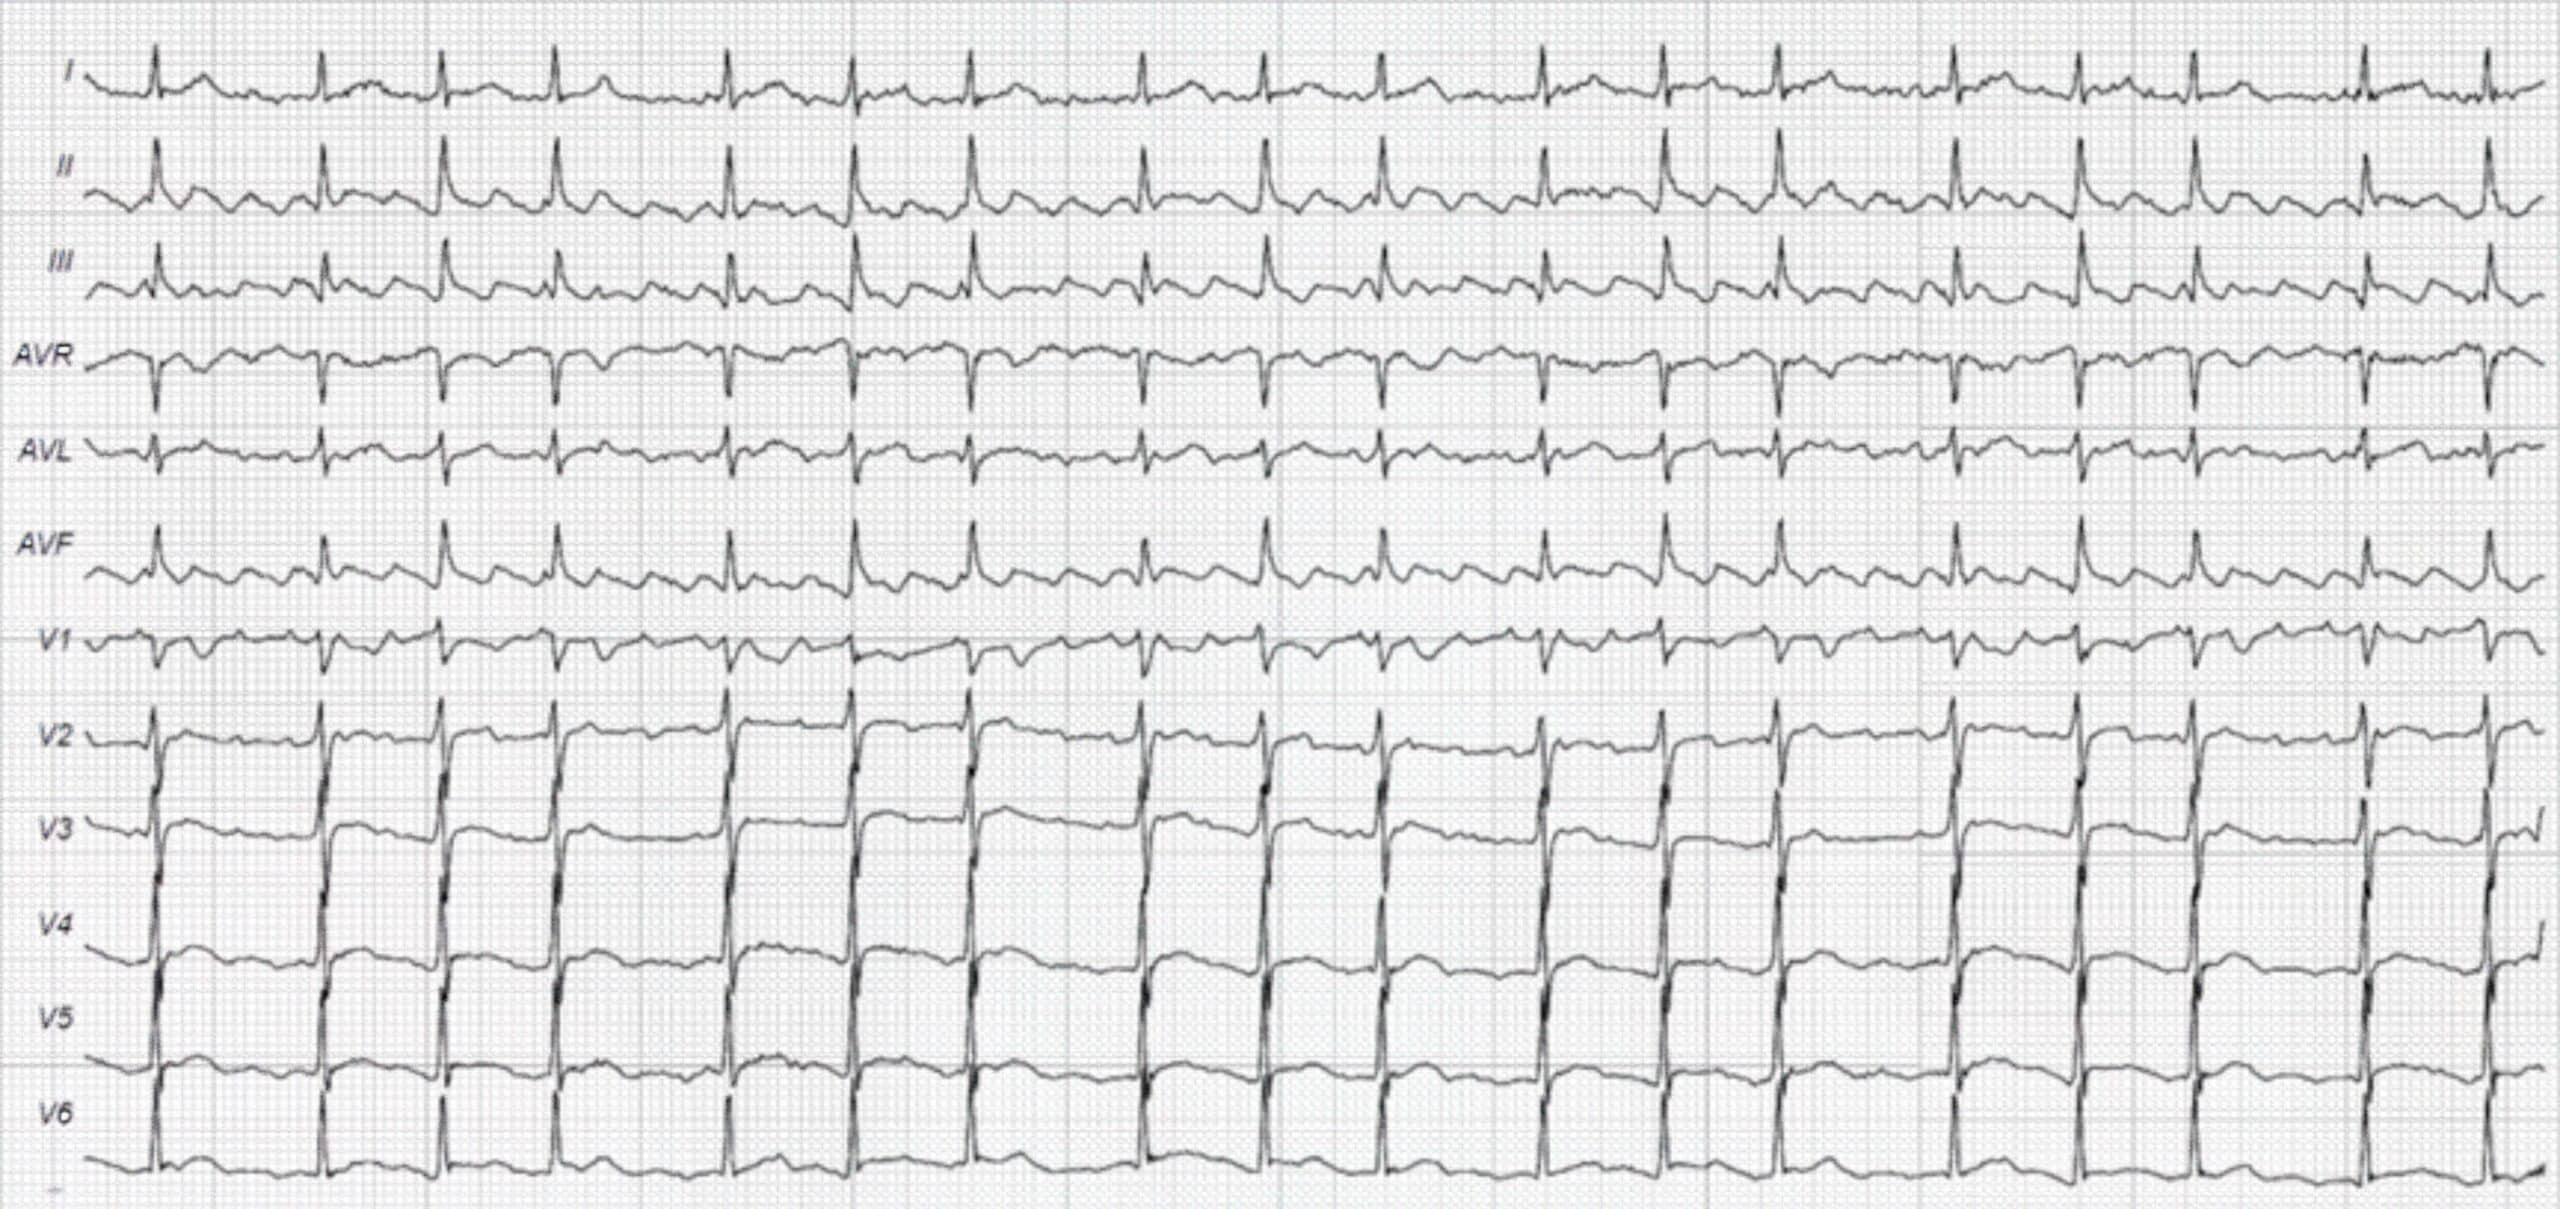

77-Year-Old Man With a History of Palpitations butOtherwise Asymptomatic ECG

Atrial flutter is more common in the older population. It can last for several beats or several years. Patients may be asymptomatic or hemodynamically unstable. Symptoms are dependent on the ventricular rate that the atrial flutter produces.

During atrial flutter, the atrial rate is 230–330 bpm and consistent. The atrial impulse is consistently blocked by the AV node in a ratio of 2:1. Consequently, the ventricular rate is kept at 130–150 bpm.

Type 1 atrial flutter is the most common and is observed in 85% of patients diagnosed with AFL. Type 1 AFL generates a “saw-tooth” appearance on ECG in limb leads II, III, and aVF. The flutter or P-like waves are also visible in precordial lead V1. The isoelectric line can no longer be delineated.

The second-degree AV block ratio varies from 2:1 to 4:1 or even higher. The ventricular rate fluctuates as the ratio of the AV block changes. A Wenckebach phenomenon may be superimposed on the ECG tracing of type 1 atrial flutter. Consequently, this can be mistaken for atrial fibrillation at first glance. With experience, one can distinguish the changes of AV conduction when studying a longer ECG strip.